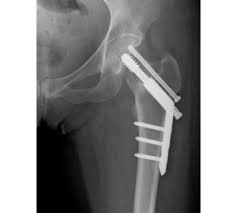

What would a physiotherapy treatment for a Hip Stress Fracture involve. Most people will need surgery to fix the fracture or replace all or part of their hip ideally on the same day theyre admitted to hospital or the day after. Treatment of hip stress fracture Immediately after a stress fracture is diagnosed the patient should discontinue all sports activities and walk with two crutches to apply less forces to the injured leg.

Eat more calcium- and vitamin D-rich foods or take supplements. This depends on the fracture site and whether it is a simple crack or a displaced fracture. Stress fractures in the hip often heal on their own especially if the fracture is small. Most orthopaedic surgeons recommend non-surgical treatments such as staying off the affected leg use of crutches and resting the hip for four to six weeks. Treatment of hip stress fracture Immediately after a stress fracture is diagnosed the patient should discontinue all sports activities and walk with two crutches to apply less forces to the injured leg. Severe fractures are usually treated with surgery. Stress injuries can be found in the shin bone foot heel hip and lower back.